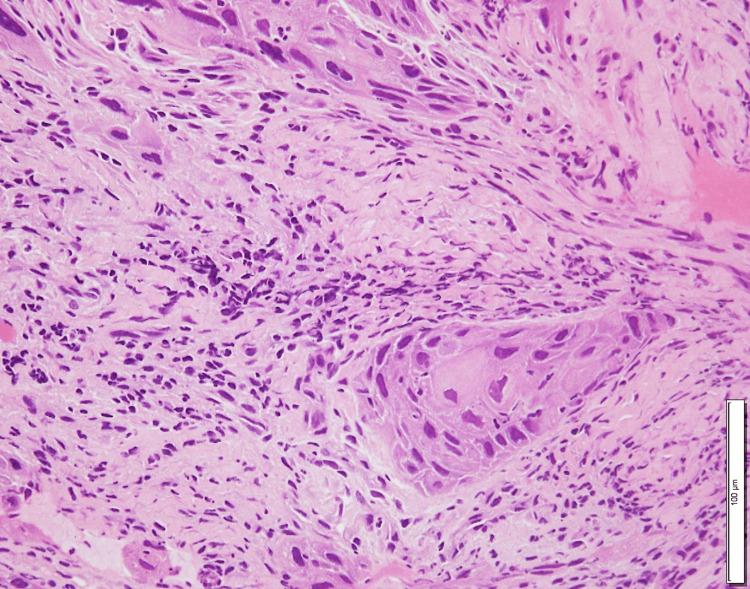

一名45岁男性,有抗NMDAR脑炎病史,表现为累及整个外耳道的右侧EACC。他的主诉是右侧耳漏。患者没有免疫功能低下。组织病理学分析证实了中度分化鳞状细胞癌的诊断(图3)。MRI显示右中颅窝硬脑膜增强,表明肿瘤浸润(图4A、4B)。根据改良的匹兹堡分类法,该疾病被归类为T4。没有证据表明颈部淋巴结受累或远处转移。患者接受了根治性同步放化疗,IMRT(70 Gy/35 Fr)联合顺铂(100 mg/m2,三个三周疗程)。

图3 标本苏木精和伊红染色显示非典型鳞状上皮细胞浸润基质,证实了中分化鳞状细胞癌的诊断